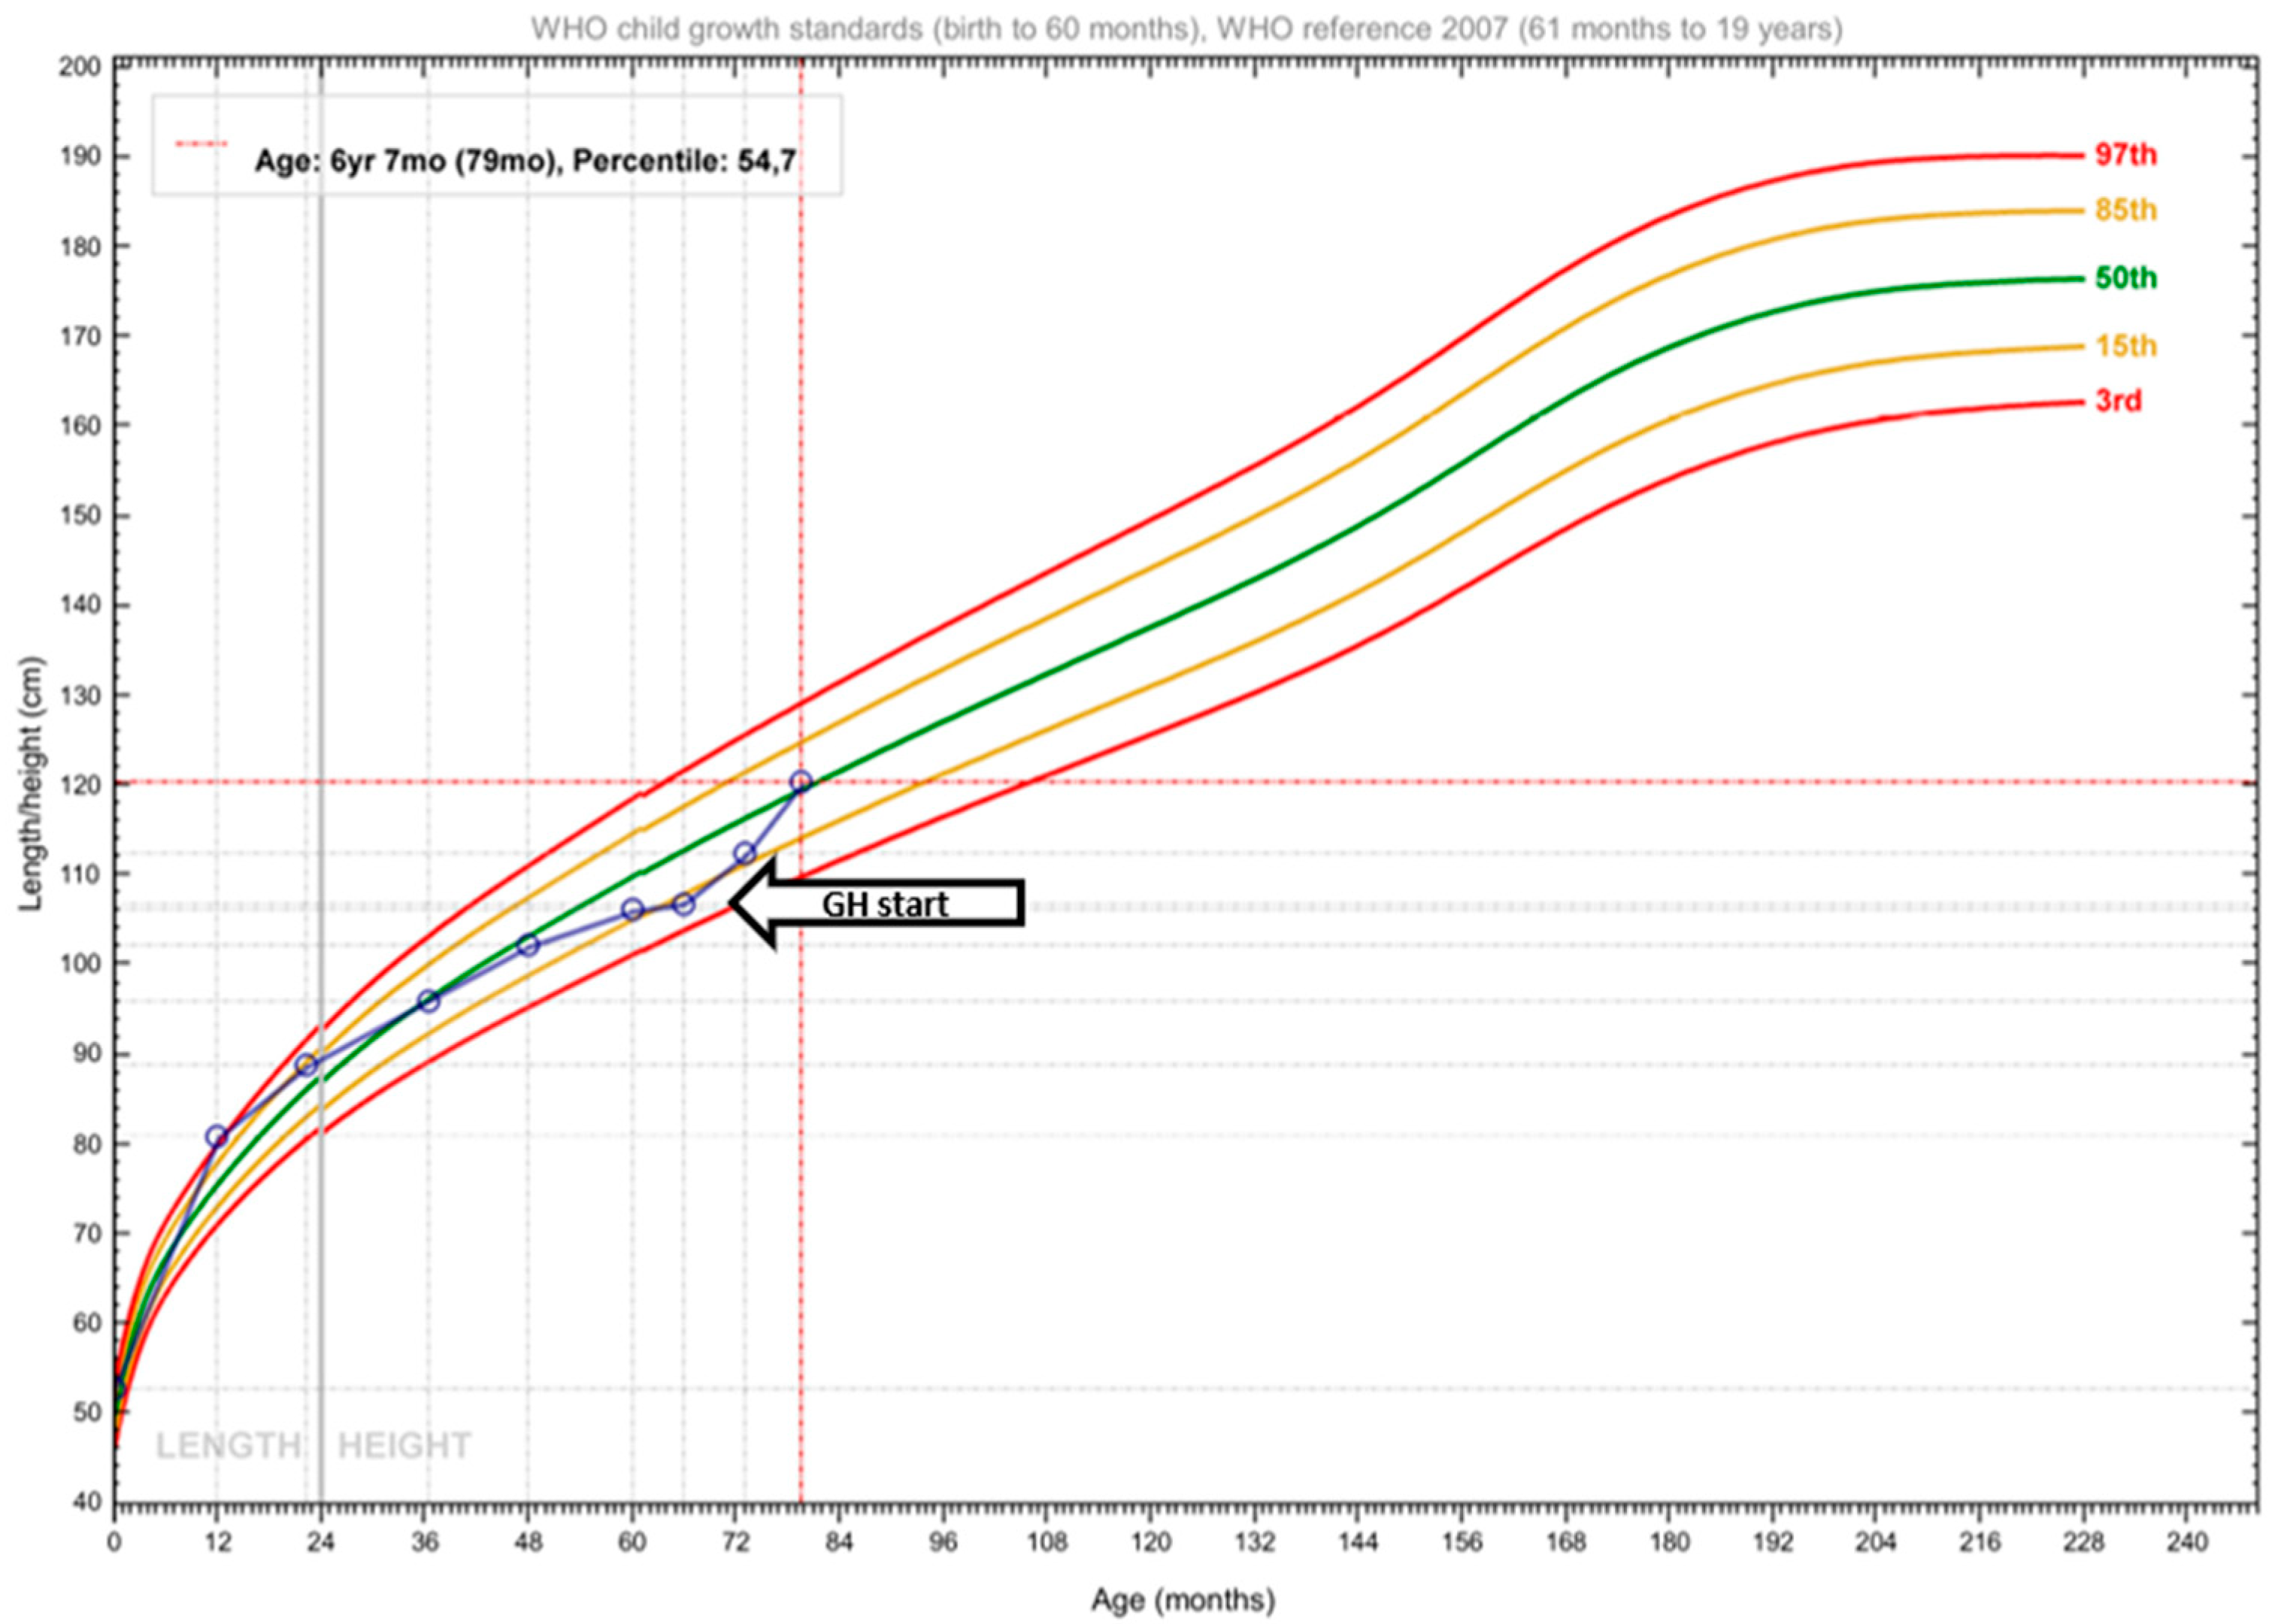

2.2. Therapeutic Intervention

2.3. Outcome and Follow-Up (10 Months)